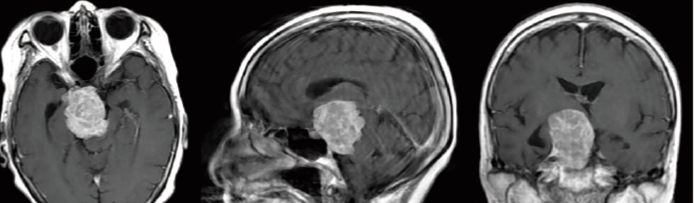

頭蓋底手術 脳腫瘍の症例

手術前

手術後

鍵穴手術 髄膜腫の症例

脳ドックで髄膜腫という脳腫瘍が見つかった患者さんの症例です。手術前のシミュレーション結果では、脳腫瘍にも鍵穴手術が可能と判断され、手術を実施。腫瘍は全摘出され、7年以上再発はありません。

(68歳・女性/ 青い矢印の部分が髄膜腫)